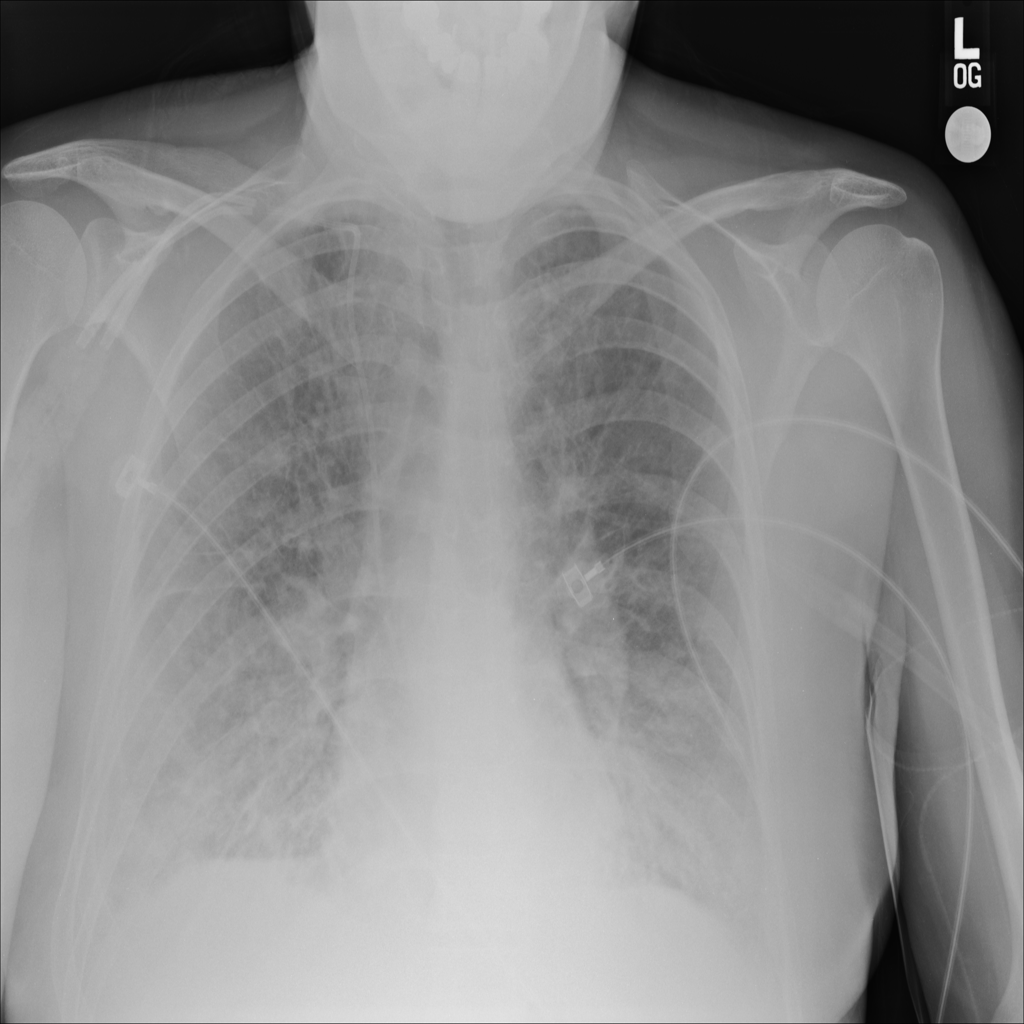

PAT-24D9 · IMG-006Edema

PAT-24D9 · IMG-006

AP